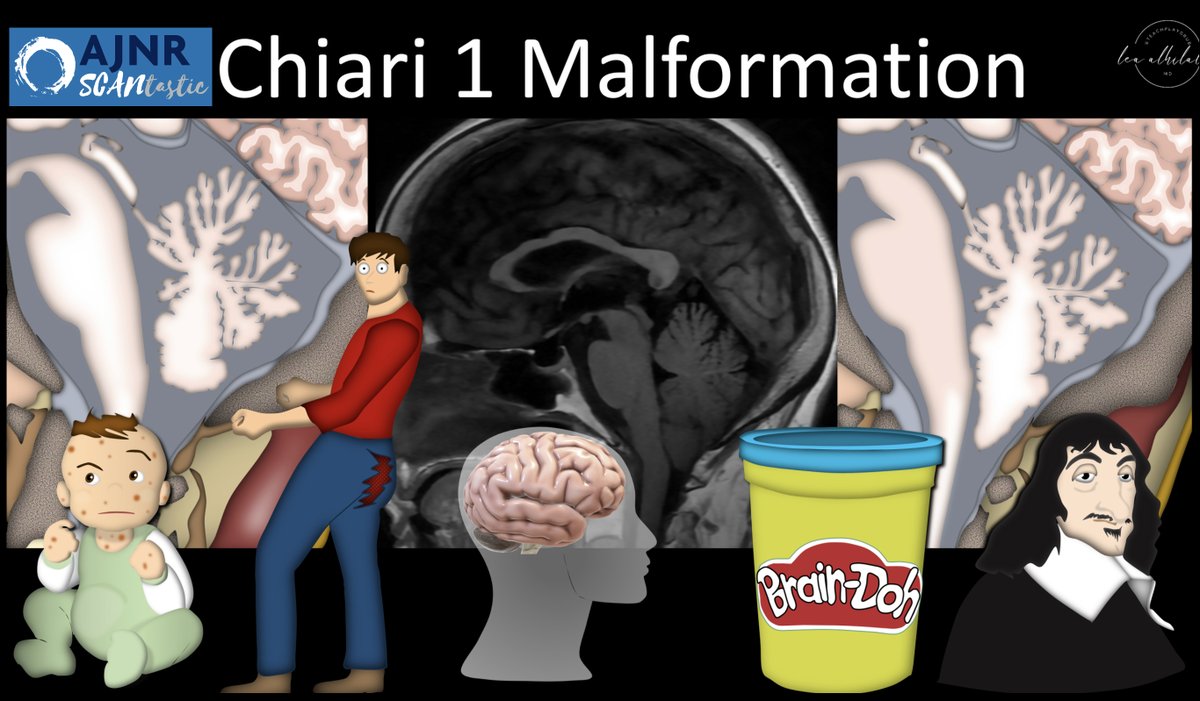

1/AJNR SCANtastic 🧵w/ Lea Alhilali, MD! Has measuring for Chiari 1 malformations become a real headache? Can’t quite peg when to call a Chiari? Looking for a better way? SCANtastic decompresses it w/new @theAJNR Chiari research: ajnr.org/content/early/…